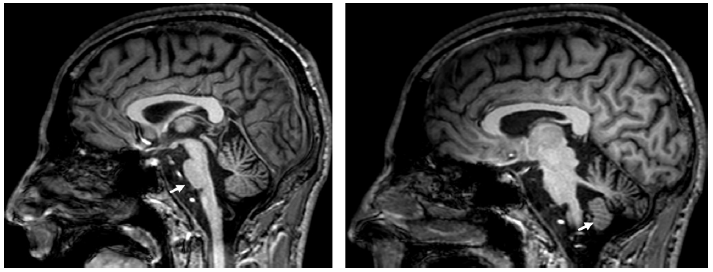

同时存在小脑性共济失调和自主神经功能障碍的主要原因是多系统萎缩(图 7),典型表现是桥脑出现“十字征”(图 8)。

图8 多系统萎缩的“十字征”。图为头颅MRI FLAIR序列图像。十字征高信号是脑桥中缝核和脑桥小脑纤维的神经元丢失所致。

表5总结了四种遗传性共济失调,这四种遗传性共济失调均很常见小脑萎缩。图9显示的是痉挛性共济失调相关的小脑萎缩。图10显示的是线粒体疾病相关的小脑萎缩。运动障碍如震颤和Kayser-Fleischer环的存在应考虑Wilson病(图11)。大多数SCA可见进行性橄榄小脑萎缩(图12和13)。

图11 Wilson病患者头颅MRI 影像。头颅MRI FLAIR序列显示Wilson病中的顶盖和小脑中脚的高信号(箭头)。

图12 患者头颅MRI 影像。头颅MRI T1加权序列显示脊髓小脑性共济失调2型(SCA2)相关的小脑萎缩。脑桥稍扁平(箭头,左侧)和小脑扁桃体保留(箭头,右侧)。

图13 患者头颅MRI 影像。头颅MRI T1加权序列矢状位图像显示脊髓小脑性共济失调2型相关的小脑和脑干萎缩。脑萎缩和脑桥扁平(箭头);可能的脊髓变细。